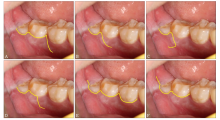

翻瓣示意图===A:标准三角瓣;B:Szmyd瓣;C:逗号形瓣;D:刺刀形瓣;E:标准封套瓣;F:Kruger封套瓣。"